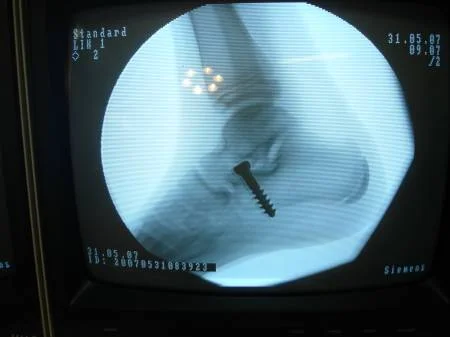

El tratamiento quirúrgico en recurso para corregir el pie plano, cuando ha fallado el tratamiento conservador. Existen muchas técnicas quirúrgicas, pero quizás la que está más difundida es la descrita por el Dr. Recaredo Álvarez en 1972, la técnica de Calcáneo Stop, la cual reconstruye la relación entre los huesos astrágalo calcáneo, sin actuar en superficies articulares, actuando en el seno del tarso constituyendo el concepto llamado artrorrisis, realizada con un tornillo especial de bloqueo.

La técnica de calcáneo stop es un procedimiento quirúrgico sencillo y ambulatorio, el cual permite corregir el pie plano valgo juvenil (8 a 12 años de edad), con excelente resultados. El paciente inicia el apoyo a las 24 horas, tendiendo a caminar metiendo los pies, lo cual es normal en las primeras semanas del postoperatorio, lo padres no deben preocuparse por este hecho.

Caso clínico: Paciente de 10 años de edad, quien presentaba pie plano valgo doloroso, con acortamiento del tendón de Aquiles (gemelos). Fue intervenido quirúrgicamente practicándose  cura operatoria según la técnica de calcáneo stop, con la colocación de tornillo de bloqueo en el seno del tarso y alargamiento del tendón de Aquiles según técnica de Vulpius. Excelente resultado postoperatorio. Ver imágeness arriba y a la derecha.